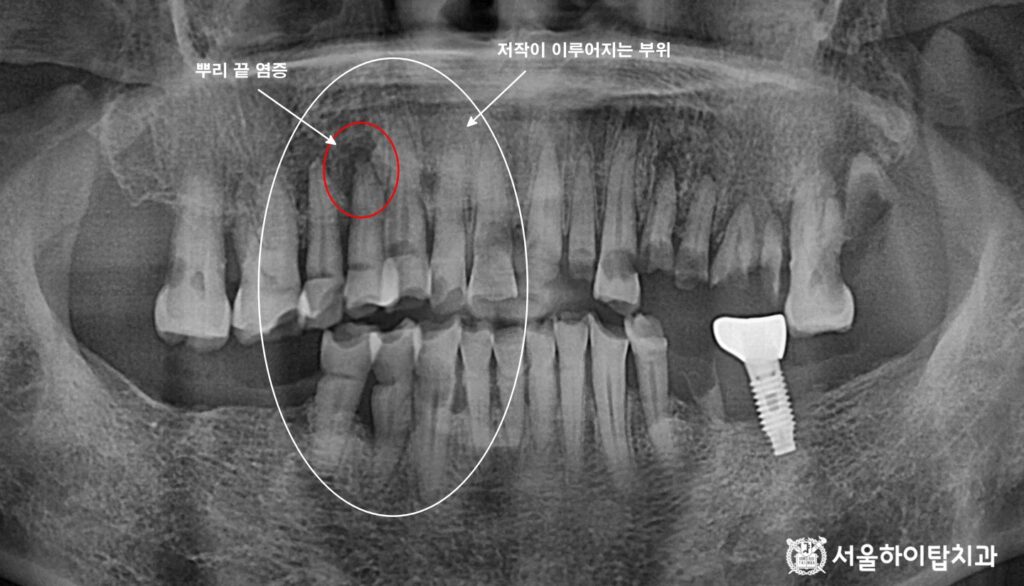

이에 따라 파노라마 엑스레이를 보면

저작이 이루어지는 치아 뿌리 끝에서

방사선 투과상으로 염증성 병소가 관찰됩니다.

여기에 더해, 전반적으로 치조골이 흡수되어

뼈의 높이가 낮아진 상태 또한 확인됩니다.

이러한 변화는 치아 동요도 증가와

통증을 유발할 가능성이 높으며,

장기적으로는 발치가 불가피한 상태임을 시사합니다.

즉, 동암역 치과 에서는 저작 불균형으로 특정 치아에 과도한 힘이 집중되면서,

단순한 마모를 넘어 치조골 손상과 염증까지 발생한 것으로 볼 수 있습니다.